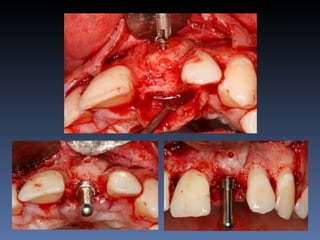

BOX 3

Vanda Alves da Silva

Idade – 51 anos

Sexo – Feminino

Raça – Caucasiana

ASA – II

Data- 26-04-2012

Diagnóstico: Desdentada parcial

Bimaxilar, periodontite 3.1

com mobilidade grau 3.

Plano de tratamento: Exodontia 3.1 , seguida de

instalação de implante com função imediata e

reabilitação provisória fixa.

Isolamento da área cirúrgica com luva estéril.